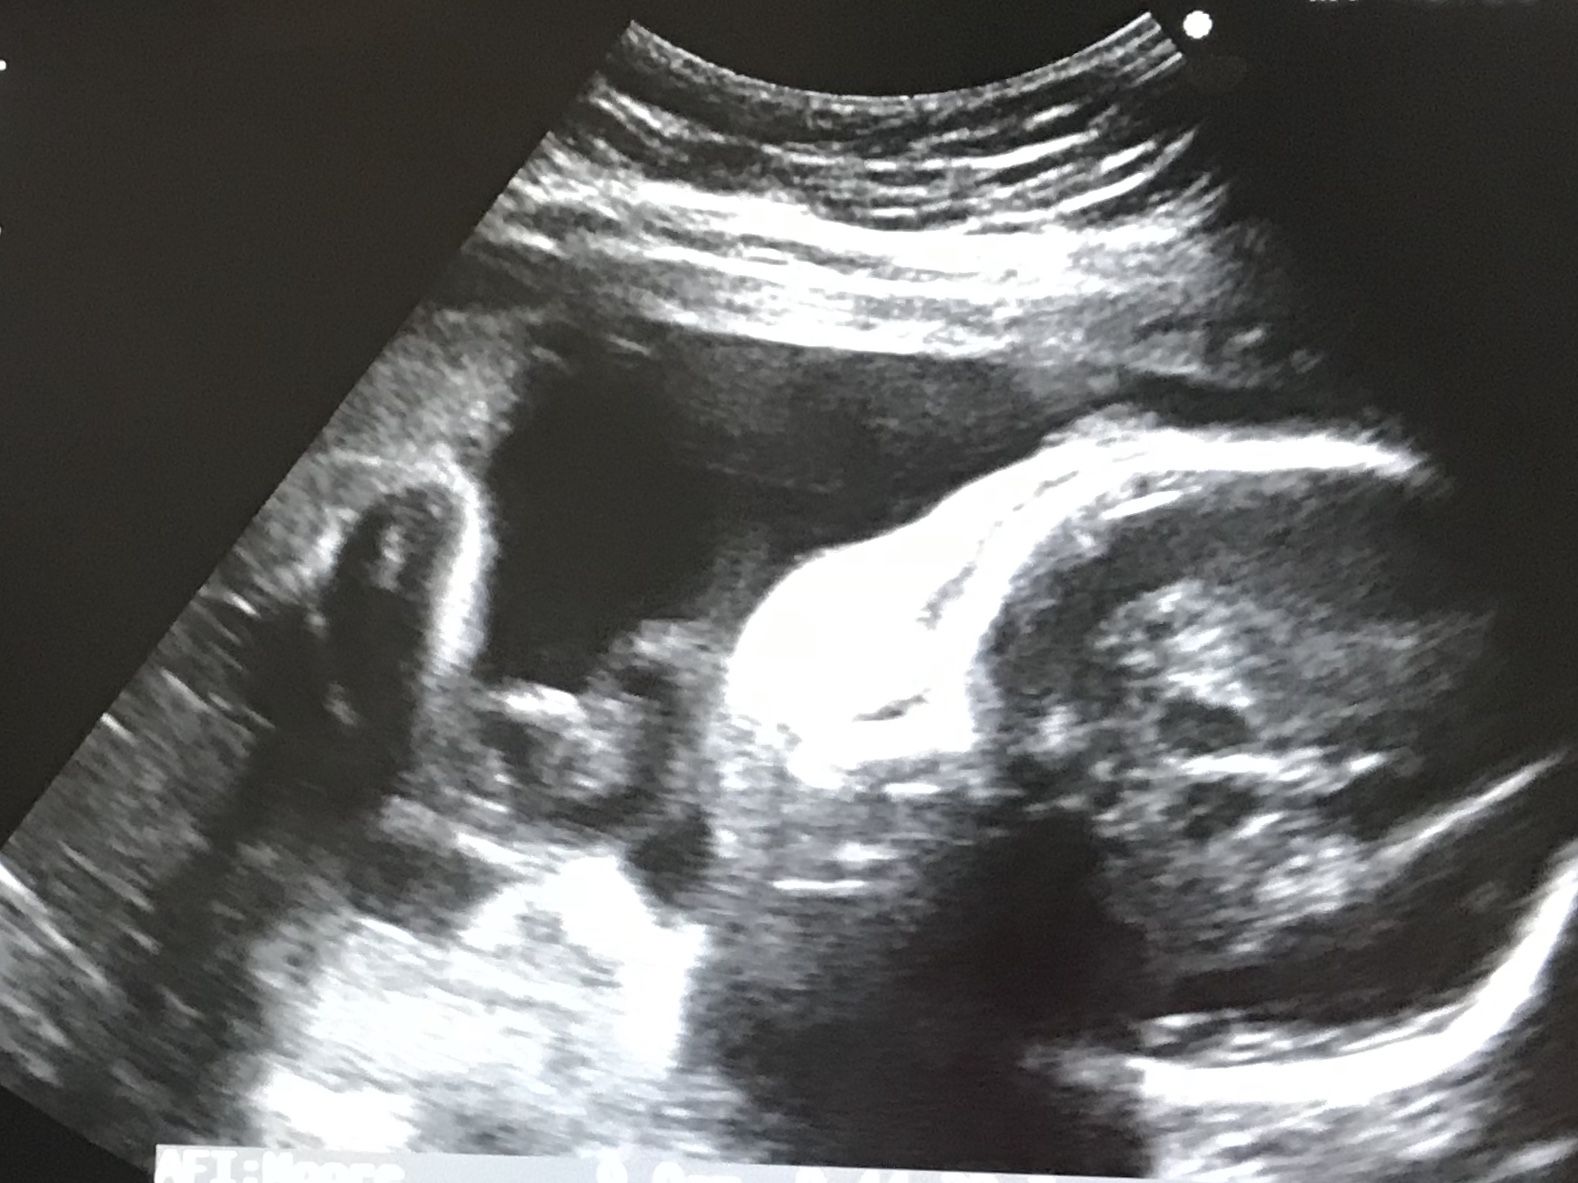

(顔がわかるようなわからないような・・・な、エコー写真。)